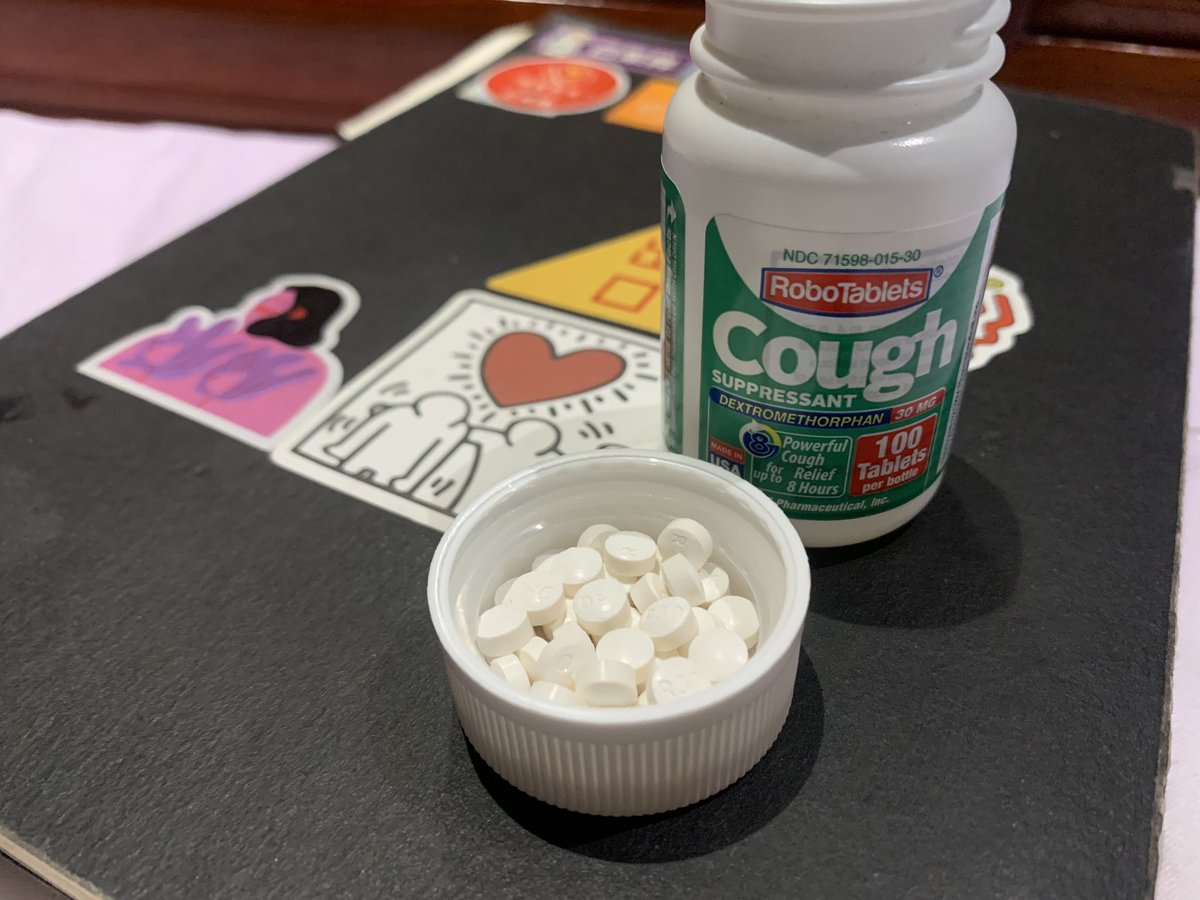

看上去像是为了描述某类特定效应而创造的术语(可能是nmda受体活性增强),用来对抗因NMDA受体拮抗剂(比如氯胺酮、DXM、PCP等)引发的解离体验(dissociation)。

看上去像是为了描述某类特定效应而创造的术语(可能是nmda受体活性增强),用来对抗因NMDA受体拮抗剂(比如氯胺酮、DXM、PCP等)引发的解离体验(dissociation)。

虽然金刚烷胺是弱NMDA拮抗剂,但长期使用可能导致:

金刚烷胺提高兴奋性毒性(NMDA活性失衡、多巴胺代谢紊乱),与致幻剂合用或交替用药会: